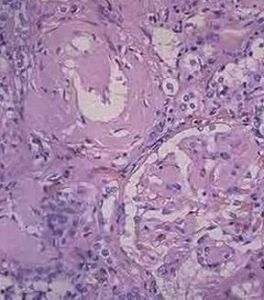

腎澱粉樣變性病理圖1.分型 澱粉樣變有幾種類型每一種可通過澱粉樣蛋白纖維的免疫化學性質來區分。這些基本的特徵是:在X線衍射檢查的β片層結構;電子顯微鏡下的細纖維非分枝表現;在剛果紅染色後,在偏光顯微鏡下的蘋果綠雙折射。根據這些生化特點,結合病理特徵及臨床表現分為6型。